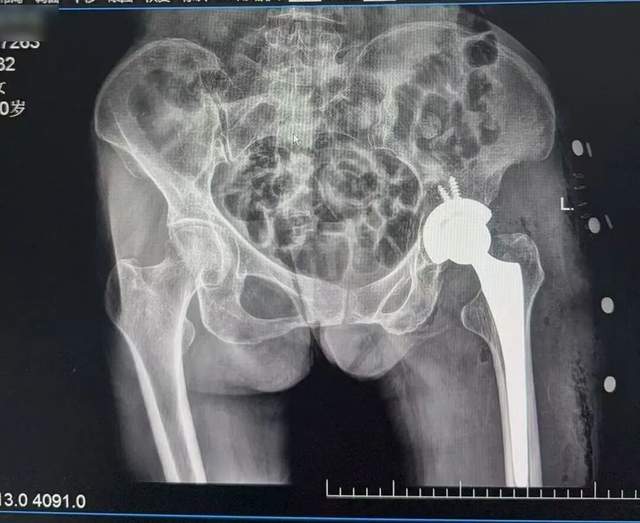

术后复查CT影像资料

由于刘阿婆本身患有慢性支气管炎和肺气肿,完善入院检查并请相关科室会诊协助诊疗后,排除了手术禁忌,在骨伤七科(关节病区)主任陈竹明的指导下,主刀的李岗副主任决定采用仰卧位直接前侧入路(DAA)。术中沿肌肉间隙进入,逐层分离、显露,适当松解、扩髓,安放合适假体。结合中医特色康复指导,患者术后第二天即可倚靠助行器下床活动,恢复迅速。这例手术的成功,展示了DAA技术在老年髋部骨折治疗中的显著优势。